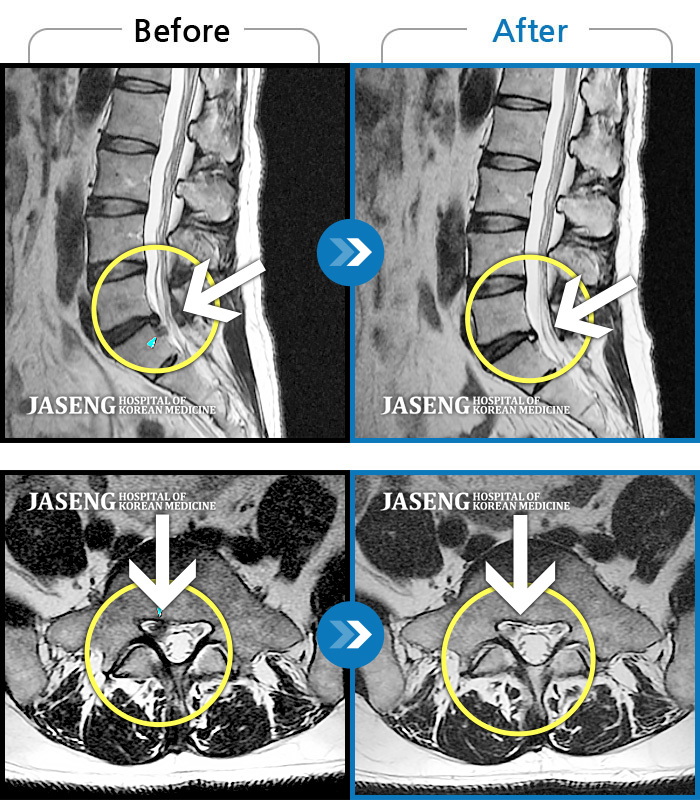

Before

After

환자에게 사전 동의를 받아 동일 조건에서 촬영되었습니다.

개인에 따라 치료 후 부작용이 발생할 수 있으니 의료진과 상담 후 치료를 진행하시기 바랍니다.

장시간 앉았다가 서면 허리 펴기 힘들고 오른쪽 종아리가 당김

우측 허리와 다리 저림